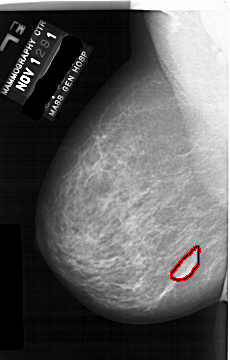

A_1691_1.LEFT_MLO

LEFT_MLO LINES 6466 PIXELS_PER_LINE 4126 BITS_PER_PIXEL 12 RESOLUTION 43.5 OVERLAY

FILE: A_1691_1.LEFT_MLO.OVERLAY

TOTAL_ABNORMALITIES 1

ABNORMALITY 1

LESION_TYPE MASS SHAPE LOBULATED MARGINS CIRCUMSCRIBED

ASSESSMENT 4

SUBTLETY 4

PATHOLOGY BENIGN

TOTAL_OUTLINES 1

BOUNDARY